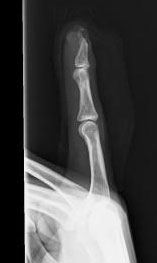

右人差し指が事故で

第一関節が潰れて抜けてしまった

骨まで潰れて

潰れて汚れきった第一関節を

綺麗に洗浄して

縫い合わせてくれたので

指を詰めた状態でなく

かろうじて第一関節が

繋がっている感じでした。